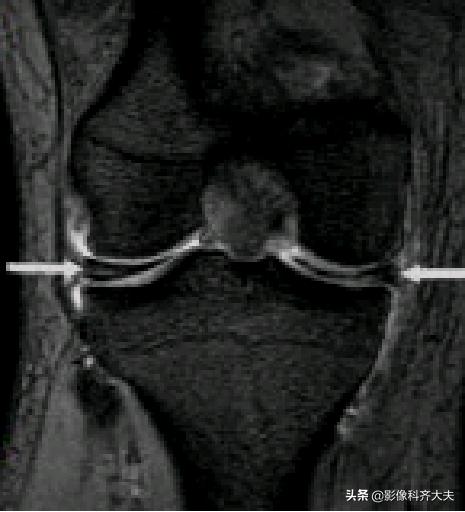

О级:为正常半月板,表现为均匀低信号且形态规则

正常外侧半月板形态、信号均匀(0级)

Ⅰ级:不与半月板关节面相接触的灶性的椭圆或球形高信号。病理:半月板粘液样变性、软骨细胞缺乏或出现少细胞区

Ⅰ级变性:球状

Ⅱ级:表现为水平的、线形的半月板内高信号,可延伸至半月板的关节囊缘,但未达到半月板的关节面缘。病理:粘液变性范围较Ⅰ级大,显微镜下软骨基质的的多细胞区内可见裂隙和胶原碎片

Ⅲ级:半月板内高信号达一个或两个关节面。Ⅲ级A型:线形高信号达关节面。Ⅲ级B型:不规则高信号达关节面。表示一个确定撕裂。可为部分性或全层撕裂。常伴有症状。病理上可见纤维软骨断裂伴或不伴肉眼可见的表面蔓延 。